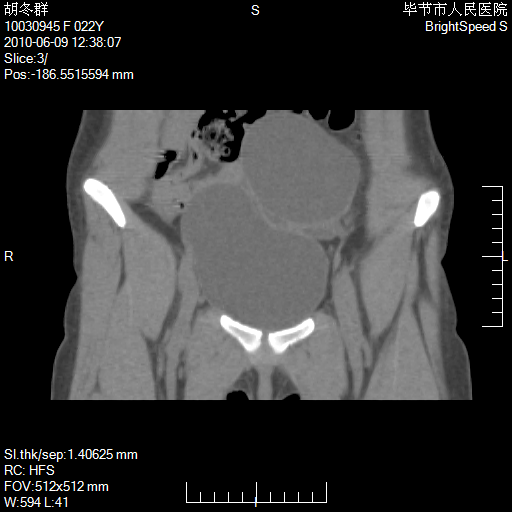

患者23岁,发现腹部包块3月。

左侧卵巢囊腺瘤或囊腺癌

盆腔内囊性占位性病变;考虑左侧卵巢囊腺瘤。

有分隔、壁薄,支持考虑左侧卵巢囊腺瘤。

左侧卵巢浆液性囊腺瘤。

支持考虑左侧卵巢囊腺瘤;宫腔积液。

有分隔、壁薄,支持考虑左侧卵巢囊腺瘤。排尿后,膀胱缩小,由于重力作用,肿块下移就到了膀胱位置,很好理解。